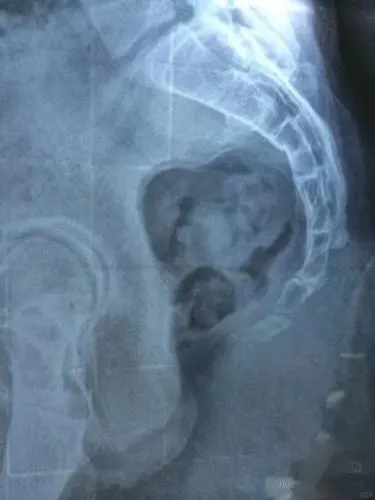

最近遇到几个个案 骨盆后倾下掉 再摸尾椎基本上都是勾进去的 其实尾椎尖下面是尾闾穴 尾闾穴是我们人体的生发之地 尾椎尖慢慢松开 骨盆会慢慢上提 而且上臀会饱满 并且股骨头的角度也会变化 最有意思的事 尾椎尖松开 肛门的紧张会释放 会不断排气以及开始排宿便 尾椎一调 身体重心会向后 原来站着总是不自觉向前顶胯骨盆前移 自然消失 而且坐着很容易坐在坐骨上 如果你练瑜伽 骨盆无论怎样练习 都很难翻上来 你一定摸摸自己的尾椎是否勾进去的 也可以拍骶尾椎侧位片发到评论区里